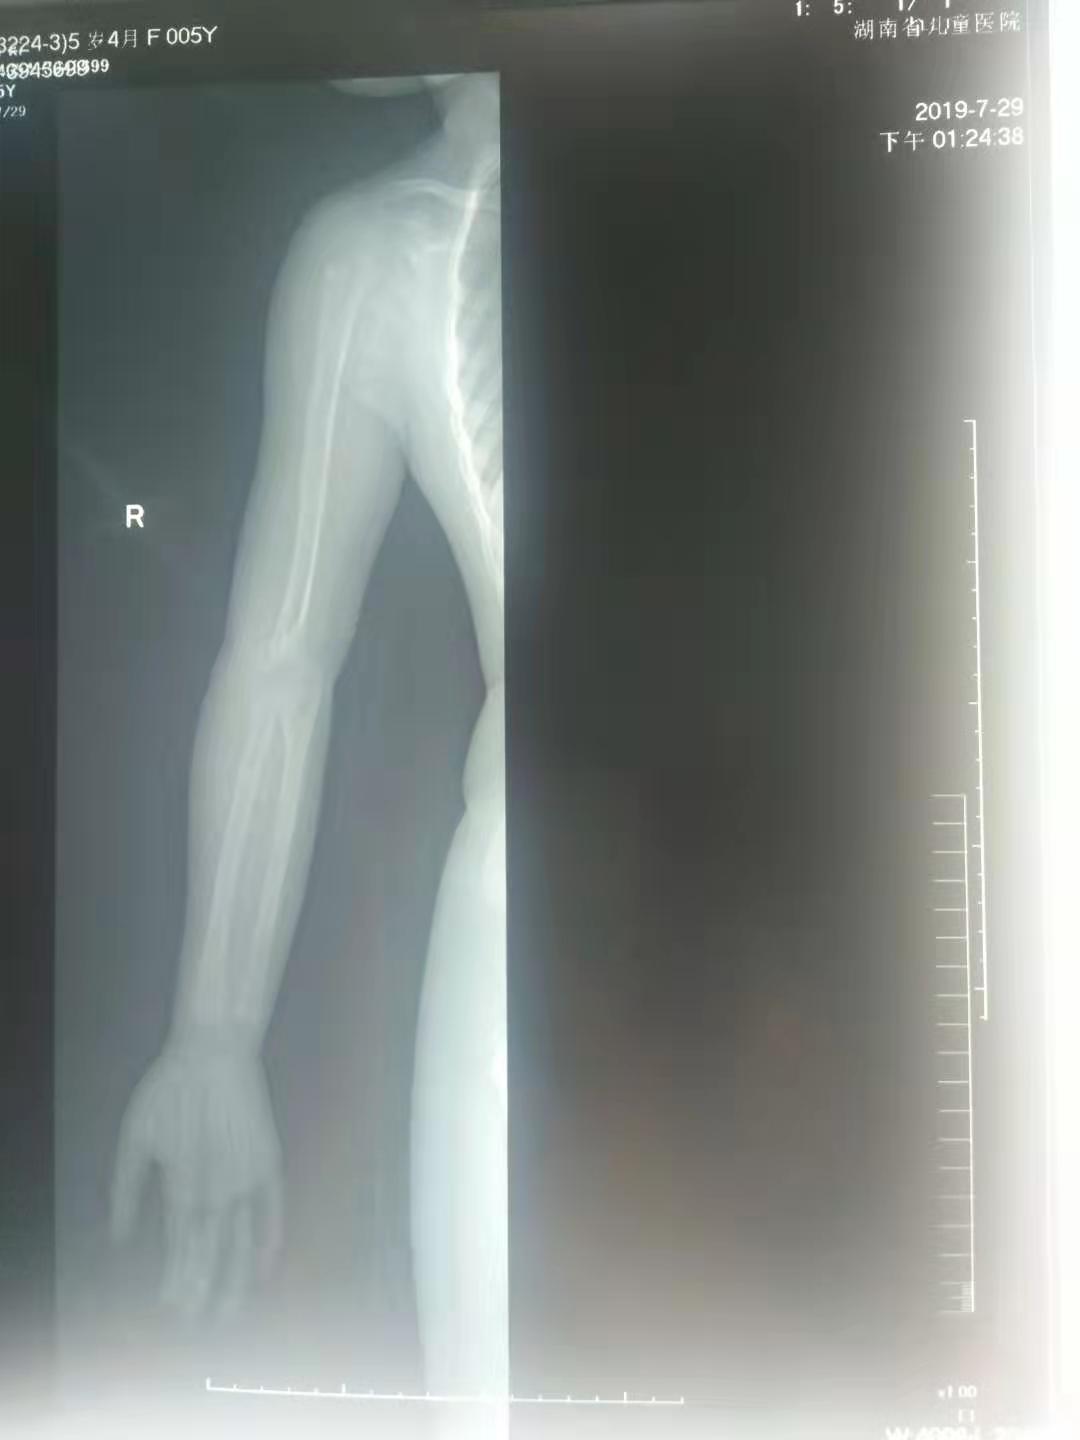

五岁的小女孩,因为小时候的意外导致了手肘骨折,当时不过一岁半的小女孩,没有及时告诉自己的妈妈,小女孩的妈妈发现了异常,小女孩手抬不起来,这可把这位妈妈给急坏了,立即带着孩子赶去了当地的医院,经过检查发现小女孩的手肘骨折错位,当时由于孩子太小,所以没有做手术,于是给予了手法复位,打了石膏,夹板;时隔两年,孩子的妈妈发现,孩子手肘与正常的手肘有些不一样,因为孩子太小,医生提议在孩子在大点的时候给予手术修型纠正。孩子的手有些畸形,没有出现什么功能障碍,只是对于一个孩子来说,影响外形。

骨折的手